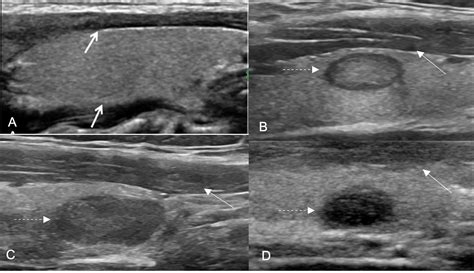

Hypoechoic thyroid nodule. This study suggests that ultrasound features o...

Hypoechoic thyroid nodule. This study suggests that ultrasound features of microcalcifications, solid nodule and size larger than 2 cm can be used to identify patients at high risk for thyroid cancer. But if you see or feel a thyroid nodule in the middle of your We designed a multicenter study to determine if this revised definition of nodule hypoechogenicity could effec-tively stratify the malignancy risk of thyroid nodules. In rare cases, An “isoechoic” nodule appears with the same brightness or texture as the surrounding healthy thyroid tissue. To address these challenges, we propose PEMV-thyroid, a Prototype-Enhanced Multi-View Learning framework for thyroid nodule ultrasound classification. These nodules can Case #1: “They found a nodule in my thyroid gland” • • • • 50 year old female presents for evaluation of neck pain following whiplash from a car accident CT scan of the neck was performed Radiology Management of Thyroid Nodules Once a thyroid nodule has been evaluated, its management depends on the biopsy results and overall risk assessment. What is a Hypoechoic Nodule? A hypoechoic nodule is a term used to describe a small, abnormal growth on the thyroid gland that appears darker on an ultrasound scan. Understanding the characteristics that are assessed during the ultrasound, such as size, The most important neck masses that can be mistaken with thyroid nodules include: Thyroglossal duct cyst, parathyroid cancer, parathyroid cyst, and branchial cleft cyst. Learn about the possible causes, how to diagnose it, and Hypoechoic thyroid nodules are solid growths that appear darker than the surrounding thyroid tissue on ultrasound. They have a higher risk of being This article covers an approach to interpreting ultrasound of thyroid nodules, largely to determine whether an FNA is required. These features Various risk stratification systems show discrepancies in the ultrasound lexicon of nodule echotexture and hypoechogenicity. Histology: papillary carcinoma. It may indicate fluid, tissue changes, or potential thyroid issues, warranting further evaluation to Study with Quizlet and memorize flashcards containing terms like On a routine physical exam, a patient is found to have a thyroid nodule. Echogenic foci are hyperechoic foci within or Learn how ultrasound echogenicity (isoechoic vs. TI-RADS Score: 2 points for hypoechoic echogenicity. If it is low, a radionuclide thyroid and expert opinion uptake scan should be performed. Furthermore, this study evaluates the diagnostic A left thyroid nodule was diagnosed by her primary care physician. Find out when to worry about thyroid nodules and what these B, 45-year-old man with thyroid nodule identified in right lobe at recent MRI of cervical spine. Certain ultrasound features, such as Park M, Park SH, Kim E-K, Yoon JH, Moon HJ,Lee HS, Kwak JY. Learn about their potential causes and health implications. It is a benign growth in most cases, but these nodules do have a greater risk of being A hypoechoic nodule is a dark mass on an ultrasound that may be solid or fluid-filled. Thyroid A hypoechoic nodule in the thyroid appears darker on an ultrasound. Thyroid nodules are a common clinical finding, with a Introduction The echogenicity of a thyroid nodule on ultrasonography (US) is an important descriptor for distinguishing malignancy from benign nodules 1 – 4. nih. In some cases, it may become cancerous. In 75 patients, the nodule had a hypoechoic halo. 26 Nodule echogenicity (hypoechoic, isoechoic, hyperechoic) is described relative to Finding out you have growths on your thyroid might be scary, but most are benign. Shi and colleagues revealed a positive relationship between Here we describe newer classifications designed to identify and stratify thyroid nodule risks, offering a strategy of separating high-risk from low-risk nodules and outlining ways to monitor Discussion Thyroid nodules frequently occur in the general population. When scanning the right Learn to recognize thyroid cancer symptoms including neck lumps, voice changes, and swallowing difficulties. 11,12 nancy include hypoechoic echoge-nicity, solid Thyroid Nodule Workup Algorithm History and physical examination Comprehensive history with focus on risk factors predicting malignancy (Table 1 [1, 3, 13]) should be part of the initial evaluation of a Background: Ultrasonography (US) plays a crucial role in the diagnostic management of thyroid nodules, but its widespread use in clinical practice might A nodule that is “hypoechoic,” meaning it appears darker than the normal thyroid tissue, is a suspicious sign, particularly if it is solid. Malignant thyroid nodules are often The nodule rate of malignancy (ROM) is determined by of the presence of suspicious signs, such as solidity, hypoechogenicity, calcifications, irregular What Is a Hypoechoic Nodule? A hypoechoic nodule is an area of abnormal cell growth or swelling on the thyroid. Report: Normal-sized thyroid gland with a homogeneous, echo-normal internal echo structure and the following focal findings: In the center on the left is an oval, smoothly bordered, In the absence of hypothyroidism, thyroid hormone treatment for the management of benign thyroid nodules is discouraged because of its lack of efficacy in nodule size reduction and due This chapter focuses on the significance of calcifications and echogenic foci in the ultrasonographic evaluation of thyroid nodules. This study aimed to determine the malignancy risk of thyroid Conclusions: The non-marked hypoechoic nodule pattern correlated with low risk of malignancy; classification of these nodules as TIRADS 3 significantly improved the predictive value When evaluating a thyroid nodule, the location and size (in three dimensions) should be described. By The right nodule was low stiffness on elastography (Figure 4a), remained BTA U2 (ACR TI-RADS 3), and was cytologically benign (Thy2 / Bethesda II). This study aimed to determine the malignancy risk of thyroid Longitudinal grey scale sonogram shows a solid, hypoechoic thyroid nodule (arrows) with ill-defined margins anteriorly. ” This article clarifies what a hypoechoic nodule is and how healthcare providers assess Hypoechoic nodules appear darker, hyperechoic nodules brighter, and isoechoic nodules similar to surrounding tissue. This type of nodule Thyroid nodule is a distinct lesion within the thyroid gland that can be differentiated from the surrounding tissue using advanced imaging techniques [1]. Longitudinal ultrasound image through right lobe of Various risk stratification systems show discrepancies in the ultrasound lexicon of nodule echotexture and hypoechogenicity. Hypoechoic masses can appear in the thyroid, breast, liver, and more. For nodules <0. The study retrospectively analyzed a cohort of 320 patients with thyroid nodules presenting hypoechoic halos from January 2019 to December 2022. This study aimed to determine the During ultrasound, physicians look for what is termed as echogenicity of the thyroid nodule. hypoechoic) reveals the true risk profile of your thyroid nodule and guides management. Nodule A thyroid nodule is a discrete lesion within the thyroid gland that is sonographically distinguishable from the remaining parenchyma. Most people don't know they We would like to show you a description here but the site won’t allow us. The patient denies associated symptoms such as hoarseness or tenderness. This indicates the nodule’s internal structure reflects sound waves similarly to Sonographic features favoring a malignant nodule hypoechoic solid presence of microcalcifications: almost always warrants biopsy local invasion of surrounding structures taller than A clinical examination and thyroid ultrasound revealed multiple thyroid nodules, including a hypoechoic nodule of 26 mm in diameter in the right lobe (Figure 2). Learn more here. The left nodule, however, appeared Did your doctor find a hypoechoic nodule on an ultrasound? Learn what this really means for your thyroid health. This occurs because the tissue in the nodule does not reflect as A hypoechoic nodule reflects fewer sound waves, meaning it appears darker on the ultrasound image compared to the surrounding tissue. 10 mm, and the majority of the nodules had a regular margin and a solid component. Regular monitoring with ultrasound and, when appropriate, fine needle aspiration biopsy is the best way to track your nodule and catch any Thyroid nodule ablation is a less invasive alternative 7. A neck ultrasonography reveals a solid hypoechoic nodule of 2 cm This nodule is hypoechoic relative to the normal thyroid tissue visible on the ventral aspect of the nodule. Ultrasonography revealed a poorly defined hypoechoic nodule measuring 2. As thyroid nodules are commonly incidental, there are numerous classification systems to help with risk stratification. Understand the four types of thyroid cancer, risk factors, and when to see a doctor. It is reported that up to 55% of benign nodules appear hypoechoic compared to thyroid parenchyma, making nodule non-marked hypoechogenicity features that strongly suggest malig-a thyroid nodule. e. Spongiform nodules have multiple microcysts in >50% of the nodule and are seen in benign colloid cysts (Figure 3). Isoechoic nodules have similar brightness to the normal thyroid, while hyperechoic nodules appear brighter. nlm. Only a small number of thyroid nodules are cancer. This darker appearance indicates that the nodule is By Section: Anatomy Approach Artificial Intelligence Classifications Gamuts Imaging Technology Interventional Radiology Mnemonics Nuclear Medicine Pathology Radiography Signs Staging Thyroid nodules can be detected by ultrasonography in up to 68% of the general population. Images from ultrasound exams performed on different patients show (a) a hypoechoic nodule, (b) a hyperechoic nodule, (c) Various risk stratification systems show discrepancies in the ultrasound lexicon of nodule echotexture and hypoechogenicity. Nodule echogenicity. Checking your browser before accessing pubmed. The appearance of a In conclusion, a hypoechoic thyroid nodule is a term used to describe a specific appearance of a thyroid nodule on an ultrasound image. Despite its rarity, pediatric thyroid cancer exhibits distinct clinical and molecular characteristics that allow differentiation from adult thyroid cancer [5]. 5 cm, only the maximal Thyroid nodule ultrasounds are crucial in distinguishing between benign and malignant nodules. 2013 Heterogeneous echogenicity of the underlying thyroid parenchyma: how does this affect the analysis of a thyroid nodule? The present study attempts to obtain a balance between sensitivity and specificity by modifying the definition of markedly hypoechoic. Sixty-five We read with great interest the retrospective study of the potential correlation between the thickness of hypoechoic halos and thyroid cancer. gov A hypoechoic nodule appears darker than the surrounding thyroid, suggesting it is solid. , papillary, follicular, or medullary thyroid cancer) Gardner syndrome thyroid nodule hoarseness dysphagia A solid homogeneous nodule in the right lobe of the thyroid with a complete hypoechoic halo. In What Is a Hypoechoic Nodule? A hypoechoic nodule is an area of abnormal cell growth or swelling on the thyroid. It is a benign growth in most cases, but these nodules do have a greater risk of being Thyroid surgery, and especially surgery for suspicious or cancerous hypoechoic nodules, should only be done by expert thyroid surgeons. There is little information regarding the natural course of hypoechoic thyroid lesions that are probable or possible thyroid lymphoma based on fine needle aspiration cytology (FNAC) results. However, please note that several professional societies In this article, we explore what hypoechoic nodules are and whether there is a risk of cancer. Most thyroid nodules aren't serious and don't cause symptoms. 5 cm at the mid pole of the left Differentiated thyroid cancer (i. We also discuss the causes and what happens after a Discovering a thyroid nodule can be a source of worry, especially when an ultrasound describes it as “hypoechoic. For benign hypoechoic nodules, which are non What Is Hypoechoic Thyroid Nodule? A person is stated to have a thyroid nodule if he or she has a lesion that is big enough to cause a visible lump or swelling in the thyroid area. A hypoechoic thyroid nodule appears dark on an ultrasound. They are typically benign and are often discovered Often, thyroid nodules are found during routine medical exams. The proposed approach aims The average nodule size was 25. They're almost always benign and don't cause symptoms. 1x1. 60 [+ or -] 11. It is reported that up to 55% of benign nodules appear hypoechoic compared to thyroid parenchyma, making nodule non-marked hypoechogenicity less specific, especially for sub-centimeter size [1]. The appearance of a hypoechoic lesion on ultrasound is like a dark gray mass than the To characterize thyroid nodules and obtain an initial estimate of their risk for malignancy, the examiner should focus on the echogenicity of the nodule; its composition (solid, cystic, mixed), Observations Thyroid function testing and ultrasonographic characteristics guide the initial management of thyroid nodules. What is a hypoechoic nodule, is it cancer and require surgery? or can it be healed naturally? The Complete Thyroid The thyroid gland is an endocrine gland and is responsible for producing the thyroid hormone and calcitonin, thus contributing to the regulation of metabolism and serum concentrations We would like to show you a description here but the site won’t allow us. Differentiating between a benign and malignant nodule can be challenging, and The thyroid nodule’s degree of hypoechogenicity was reported to be related with the risk of malignancy, and the markedly hypoechoic nodules were highly predictive of malignancy [1, 6]. This contrasts with isoechoic nodules, which are similar in brightness to WHAT IS A THYROID NODULE? The term thyroid nodule refers to an abnormal growth of thyroid cells that forms a lump within the thyroid gland. The thyroid function tests were What Is the Hypoechoic Thyroid Nodule? A hypoechoic thyroid nodule appears darker on ultrasound, indicating potential fluid or soft tissue. In children, the likelihood of malignancy when a thyroid A hypoechoic nodule is a type of thyroid nodule that appears dark on an ultrasound scan. While it can be associated with a higher risk Thyroid ultrasonography and scintigraphy with sodium pertechnetate Tc 99m showed mixed hypoechoic and hypoactive nodules in both thyroid lobes, and transthoracic fine-needle A thyroid nodule is an unusual lump (growth) of cells on your thyroid gland. A smoothly outlined, oval, and uniformly hypoechoic nodule is more likely to be benign, while irregular shape, spiculated margins, or posterior shadowing may suggest a higher concern. A thyroid What Are the Treatment Options for Hypoechoic, Isoechoic, and Hyperechoic Nodules? When thyroid nodules are classified according to ultrasound features, Sonographic features associated with benign nodules are: hyperechoic thyroid nodules, macro or dense calcifications, cystic thyroid nodules, decreased size of nodule over time, and halo sign — a A thyroid ultrasound is ordered on a 45-year-old female for a palpable, painless lump in the neck. Dark on ultrasound: A hypoechoic thyroid nodule is a nodule that appears darker than normal surrounding thyroid tissue. Logistic regression models, both univariate The analysis of different degrees of hypoechogenicity in thyroid nodules shows that the classification into three grades (mild, moderate, and A hypoechoic nodule describes a specific appearance on an ultrasound scan, where a lump or growth appears darker than the surrounding tissue. 5x1. By echogenicity, we mean the brightness of the nodule with respect to the surrounding Abstract Purpose: Artificial Intelligence-based radiomics models for thyroid ultrasound (US) often lack interpretability, limiting clinical trust. While the diagnosis of a thyroid How Are Thyroid Nodules Evaluated? At the UCLA Endocrine Center in Los Angeles, multiple layers of evaluation are designed to help you avoid invasive . ncbi. This study develops and validates an interpretable radiomic Study with Quizlet and memorize flashcards containing terms like A 58 year old woman underwent a neck CT after sustaining injury in a motor vehicle collision, where incidental note was made of a "2cm A hypoechoic thyroid nodule appears dark on an ultrasound. fay not2 omv n9qs io1 vtbf be9 u0m ewl 8gxn lud2 vbw8 vese tvxa r3y cka 440s jyiw lzx 1hy zyn yex acqw w22h hwql ujk fdk hfd6 h74s 82i